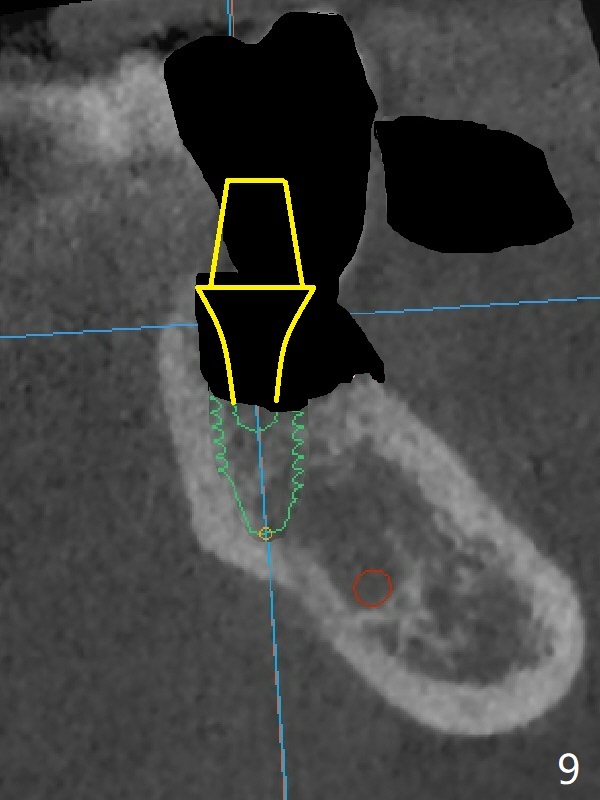

In contrast without implantation after extraction (Fig.6 (ignore green)), the socket may be grafted (Fig.7 pink circles) and covered by PRF membrane (red line). Due to the large socket with severe buccal defect, the graft is more likely to be lost (Fig.8). Several months later, an implant to be placed (Fig.9 green) will be short with unfavorable crown/implant ratio.